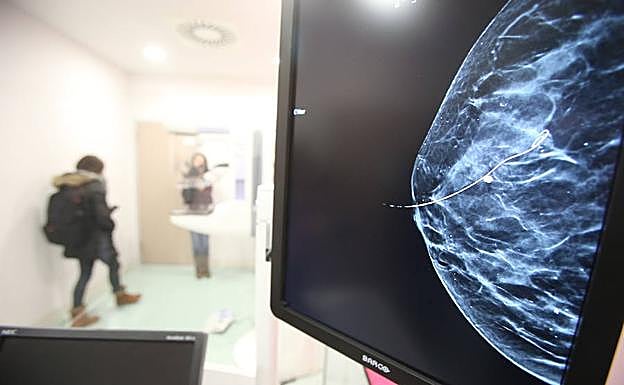

Imagen de una mMamografía.